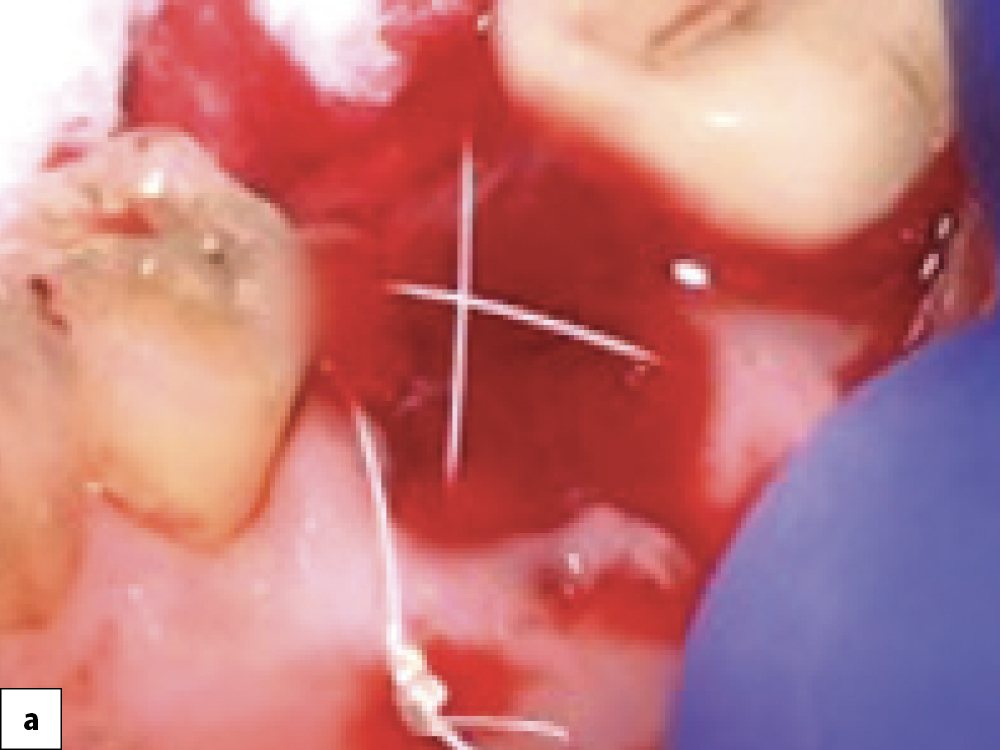

Bony Defect Evaluation A

Bony Defect Evaluation B

Bony Defect Evaluation C

Bony defect evaluation: (a) Flap reflection allows the clinician to visually evaluate the size and location of the fenestration to determine whether the defect will compromise implant positioning or primary stability when immediate implant placement is desired; (b) Examples of a large fenestration (green arrow) and loss of the buccal plate (blue arrow), either of which would contraindicate immediate implant placement due to the inability to obtain primary stability; (c) Additional example of flap reflection to show the fenestration.